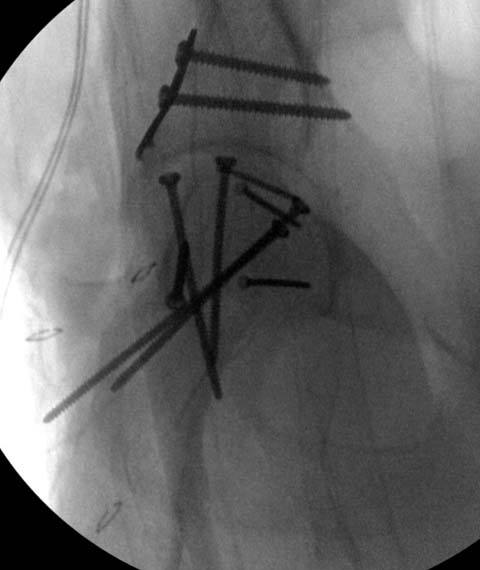

Далее перевод к нам в Травмоцентр и 03.03.2015. через 8 дней операция, выполнен остеосинтез головки 3-мя самокомпрессирующими винтами Autofix под разными углами с погружением в субхондральный слой. Доступ Kocher-Langenbeck с флип-остеотомией большого вертела и задним хирургическим вывихом головки бедра. В полости сустава два свободно-лежачих фрагмента хряща головки, которые были удалены. На снимках виден дефект хряща головки после репозиции. Небольшой фрагмент заднего края фиксирован двумя спонгиозными винтами. Далее шов раны с дренированием. На 2 сутки пациент поворачивался на здоровый бок с валиком между ног, на 4 сутки сидел в кровати и на 6 сутки ходил с помощью костылей.

Доступ выбирается на основании КТ, и ориентируются по расположению фрагментов. При расположении спереди - Smith Petersen или Watson Jones, а задние из Koher-Langenbeck. Все доступы имеют свои недостатки, повреждение медиальной артерии повышает риск, потому что больше чем 80% кровоснабжения головки за счет medial Circumflex!

Работая с Jeff Mast в конце 90х я был свидетелем разработки Flip Trochanteric Approach, где Reinhold Ganz с Jeff стали применять доступ для работы внутри впадины. Впоследствии диссертационная работа Katharine Ganz, дочери Ganzа, по изучению медиальной артерии подтвердила, что знание топографии позволяет оперировать внутри ацетабулума без риска аваскулярного некроза!

Доступ позволяет сохранить не только артерию, но также Vastus lateralis и Gluteus (второе название доступа Digastric доступ). Только при остеотомии вертела надо проявить осторожность, там сзади находится артерия! Кстати, во время операции проверяю кровеснабжение в головке лазерным доплером, но последнее время я перешел на более дешевый ICP (Intracranial Pressure Monitor)

Здесь клинические примеры: Первый случай передний доступ, второй с ICP monitor Flipp Trochanteris

и с переломом заднего края.